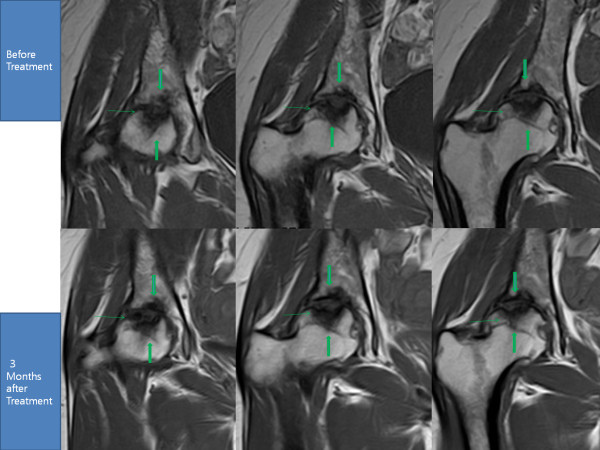

- J. Pak, “Regeneration of human bones in hip osteonecrosis and human cartilage in knee osteoarthritis with autologous adipose-tissue-derived stem cells: a case series,” Journal of Medical Case Reports, vol. 5, p. 296, 2011. View at Publisher · View at Google Scholar · View at Scopus